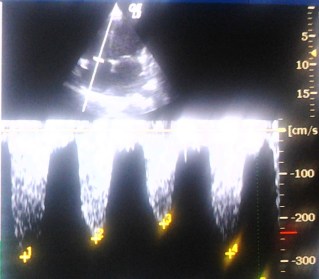

And  now  , we have observed a new echocardiographic  sign   ie  TR jet alternans  in patient with  DCM .

Note the changing TR velocity implying severe RV contractile dysfunction.